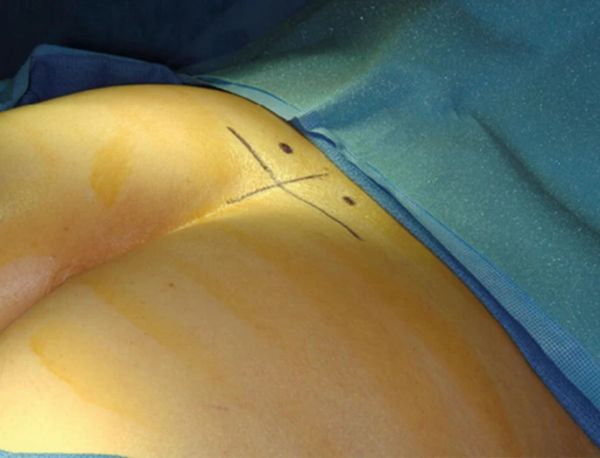

3.在透视的帮助下,使用定向导丝定位标有垂直线的中线。然后识别骶髂关节和棘突的交叉点并用横线标记。这定义了 S3 孔的区域(图10.1)。

4.如果 S3 孔在透视前/后视图中清晰可见,则标记孔的上部内侧(图10.2)。

5.如果由于覆盖肠内容物而无法识别 S3 孔,则从两条线交叉点上方约 2 厘米和 3 厘米(取决于体型)开始(参见步骤 #3)。将其标记在右侧和左侧(图10.2)。

图 10.1

FSLP 穿刺点的识别。

图 10.2

识别 S3 孔的内侧。